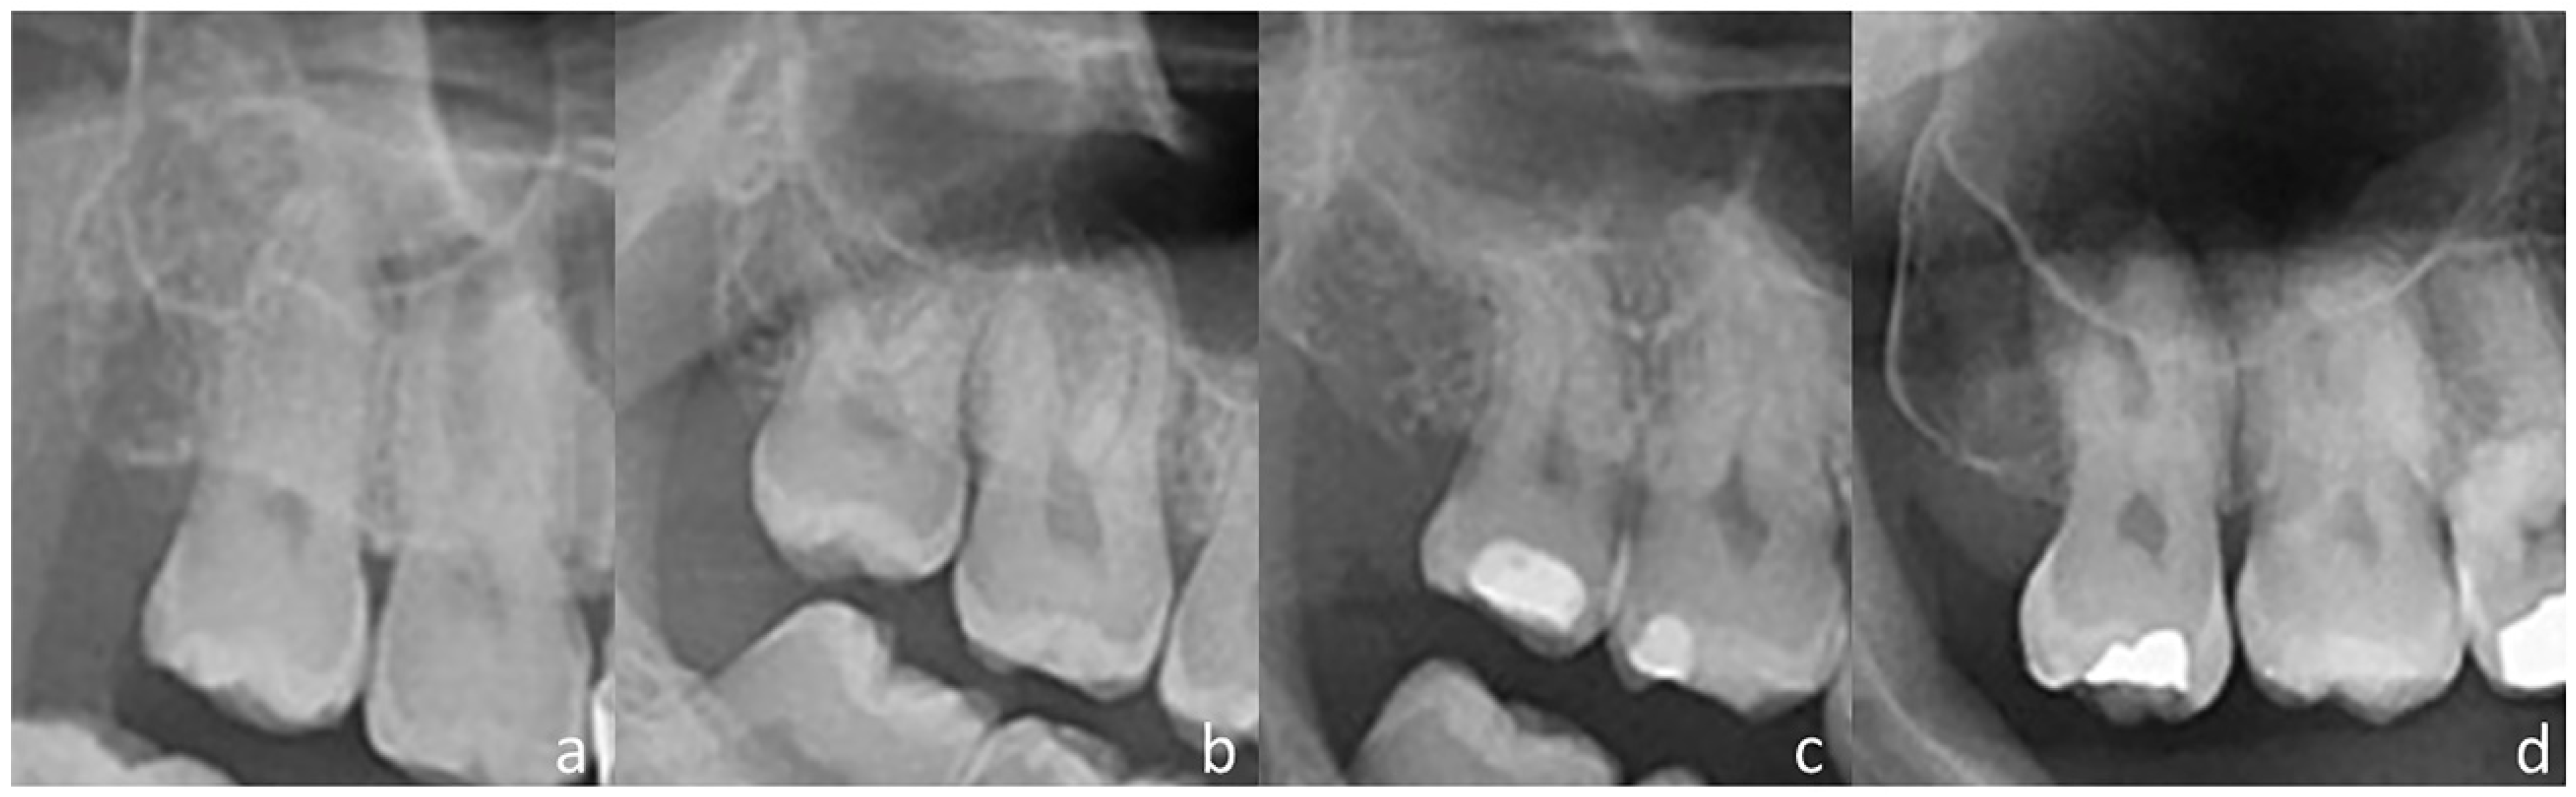

| 1 Root | 2 Roots | 3 Roots | 4 Roots | ||

| 1 root | 39 (18.9%) | 14 (6.8%) | 13 (6.3%) | 2 (1.0%) | 68 (33.0%) |

| 2 roots | 13 (6.3%) | 14 (6.8%) | 39 (18.9%) | 2 (1.0%) | 68 (33.0%) |

| 3 roots | 4 (1.9%) | 3 (1.5%) | 59 (28.6%) | 4 (1.9%) | 70 (34.0%) |

| 4 roots | 0 (0.0%) | 0 (0.0%) | 0 (0.0%) | 0 (0.0%) | 0 (0.0%) |

| Total | 56 (27.8%) | 31 (15.0%) | 111 (53.9%) | 8 (3.9%) | 206 (100.0%) |